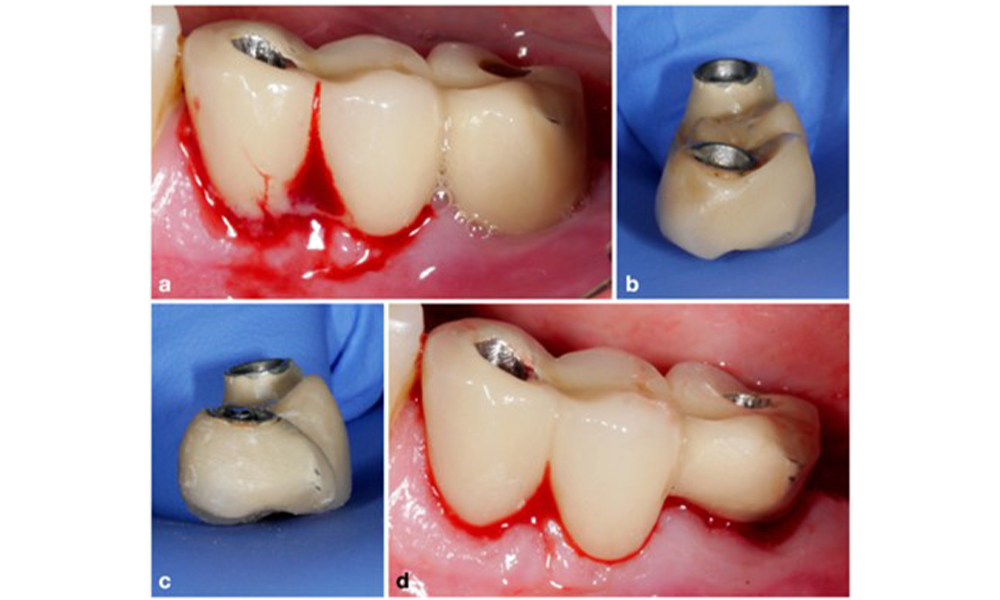

The prosthetic restoration should be removed during both non-surgical and surgical treatment to improve access to the implant surface. The choice of surgical intervention (e.g., resective, reconstructive, or combined) depends on several factors: (1) defect morphology (e.g., horizontal, dehiscence, intra-osseous, or combined) (figure 10), (2) implant surface (i.e., turned or modified/”rough”), and (3) presence or absence of sufficient keratinised and attached mucosa.